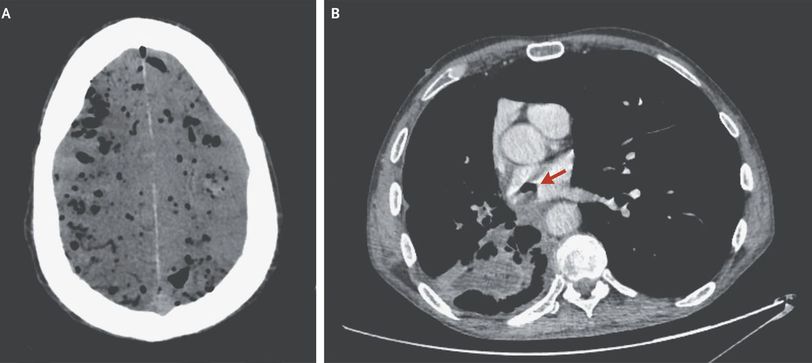

A 61-year-old man with a history of stage IIIB squamous-cell carcinoma of the lung began to have seizurelike activity while he was undergoing restaging computed tomography (CT) in the hospital. He had a known primary cavitary lesion in the right lower lobe and had previously received three cycles of carboplatin and nanoparticle albumin-bound paclitaxel (Abraxane). He was transported to the emergency department. Sudden respiratory failure and confusion developed, which resulted in emergency intubation. CT of the head revealed diffuse pneumocephalus (Panel A). The restaging CT scan of the chest showed that the previously identified cavitary lesion had formed a fistula between a bronchus in the right lower lobe and the left atrium (Panel B, arrow). The pneumocephalus was thought to have been due to an air embolism that had originated from the bronchoatrial fistula. The patient later died in the intensive care unit.